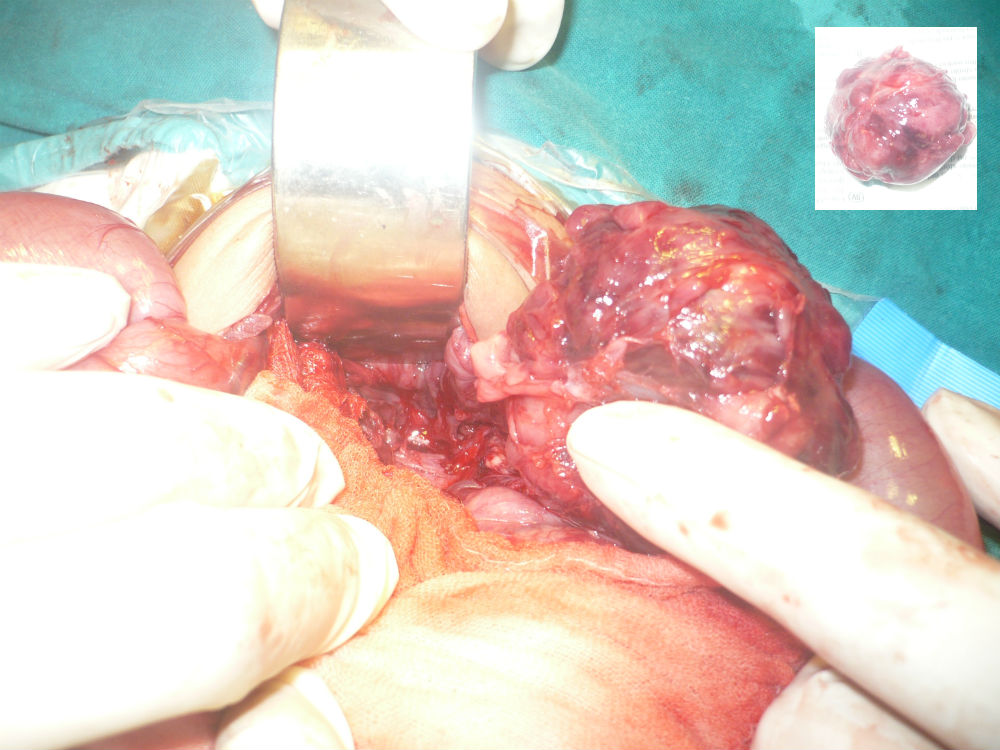

In some cases with calcifications in the mass, the differentials are further converged to sacrococcygeal teratoma and rarely presacral neuroblastoma.[4.5] Problem arises when AFP is inconclusive of SCT. Raveenthiran [5] called SCT as great masquerader. However, sometimes the inverse may be true. We had a 25-days-old male baby presented with constipation and a palpable mass in the pelvis. Ultrasound and CT scan showed calcifications in the mass. The CT scan opinion was type-IV SCT (Fig. 2). The patient was explored from lower abdominal incision. The mass was dissected retro-rectally and surprisingly entire mass was excised in-toto attached to a nerve fiber (Fig. 3). It was decided to postpone the coccygectomy till the biopsy confirmation as the mass was firm (less suspicious of SCT in setting of normal AFP) and attached to a nerve. Biopsy was suggestive of neuroblastoma.

Figure 3: Presacral neuroblastoma. Inset shows complete excision. |